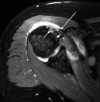

A 22-year-old professional baseball catcher has posterior shoulder pain and severe external rotation weakness with the arm in adduction. Radiographs are normal. MRI scans are shown in Figures 1 through 3. Management should consist of

arthroscopic repair and decompression. The MRI scans reveal a large posterior paralabral cyst associated with a posterior-superior labral tear. The cyst appears as a well-defined, smoothly marginated mass with low signal intensity on T1-weighted MRI scans and with high signal intensity on T2-weighted MRI scans. MRI also reveals changes in the supraspinatus and infraspinatus muscles secondary to denervation, including decreased muscle bulk and fatty infiltration. MRI has the added advantage, compared with other imaging modalities, of detecting intra-articular lesions, such as labral tears, which are frequently associated with ganglion cysts of the shoulder. In this case of a professional baseball player with a space-occupying lesion causing nerve compression with an associated labral tear, the treatment of choice is arthroscopic decompression of the cyst and repair of the tear.